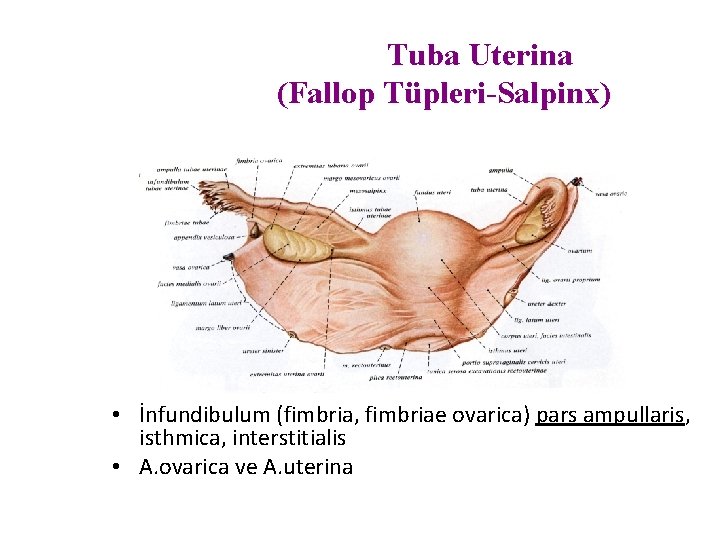

Tuba Uterina (Fallop Tüpleri-Salpinx) • İnfundibulum (fimbria, fimbriae ovarica) pars ampullaris, isthmica, interstitialis • A. ovarica ve A. uterina